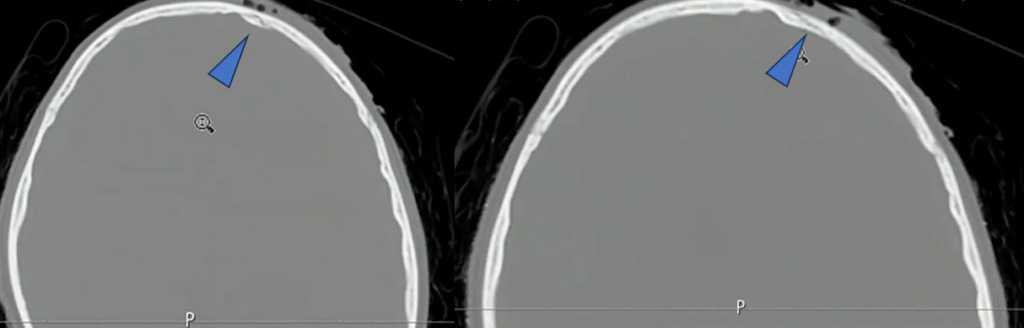

これを踏まえて、もう一度、骨条件の画像を確認しました。

一見すると異常が分かりにくい画像でも、3D画像を確認することで骨折の存在が明確になりました。

小児は骨が柔らかいため、外板のみが折れて陥没し、完全骨折に至らず所見が目立ちにくいことがあります。出血も初期は少量で、時間経過とともに明瞭化しました。本症例は外傷性陥没骨折、外傷性くも膜下出血・硬膜下血腫、脳挫傷と診断されました。